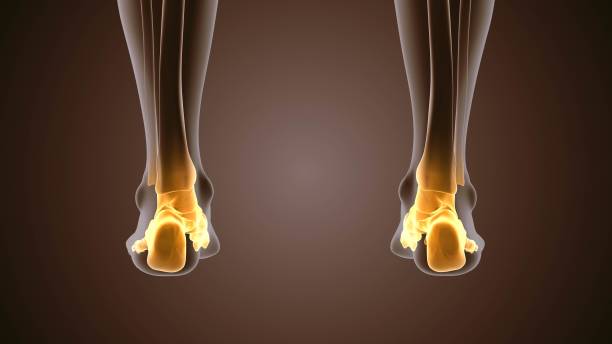

발뒤꿈치가 아픈 이유 첫 번째는 족저근막염입니다. 족저근막은 발뒤꿈치 뼈에서 시작하여 발바닥 앞쪽으로 연결되는 두껍고 강한 섬유질 띠입니다. 족저근막은 우리 몸의 중요한 역할을 하는데 아치 모양의 모양새는 우리 몸의 체중을 흡수하기 때문에 걷는 데 중요한 역할을 할 수 있습니다. 족저근막염은 이러한 족저근막에 반복되는 충격으로 근막을 둘러싸고 있는 콜라겐이 변성하면서 염증이 생긴 것을 의미합니다.

이러한 증상은 원래부터 평발이거나 걸음걸이나 생활습관 등으로 발이 변형되며 구조적으로 이상이 생겨서 문제가 생길 수도 있지만 기본적으로 하체 사용을 무리하게 하다보면 문제가 생기게 됩니다. 족저근막염 통증은 개인에 따라 다르지만 기본적으로 발뒤꿈치에 통증을 느끼게 되고 특히 아침 기상후 첫 걸음부터 통증이 나기 때문에 조기에 치료를 받는 것이 중요합니다.